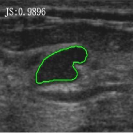

4.5 Comparison with breast ultrasound images segmentation

Unlike MR images mentioned above, ultrasound images offer real-time imaging but usually have lower resolution and contrast, making it difficult to differentiate between adjacent tissues and often introducing artifacts and noise that complicate segmentation. However, the RefLSM is robust to high levels of noise and intensity inhomogeneity, regardless of the type of medical image. To validate this, we perform segmentation comparison experiments on breast ultrasound images and calculate the Dice coefficient and Precision values for all models under evaluation.

In Fig. 10, the 1st row displays original images and initial contours for the RefLSM, while the second row shows the RefLSM’s segmentation results. Even with high levels of noise and severe intensity inhomogeneity caused by acoustic shadowing and motion artifacts, our model successfully identifies object edges, achieving an average Precision value of 0.9812. Table 4 shows that the RefLSM requires no more than 10 iterations and has an average processing time of only 1.79 seconds to segment images in Fig. 10.

To further validate the effectiveness of our model, we compared it with the ICTM, RESLS, and ALF models, represented in the 2nd, 3rd, and 4th rows of Fig. 11, respectively. The 5th row displays our proposed model. To better compare the segmentation results, we presented the initial contours in the 1st row, and the ground truth in the 6th row. We can observe that the ALF model struggles with boundary identification and has significant misclassification due to the boundary confusion in ultrasound images commonly caused by overlapping of soft tissues. While the ICTM and RESLS models perform well in some cases like column 1,4, and 7, they still face under-segmentation and over-segmentation problems when images are low contrast or have complex edges like column 1, 3 and 5. In addition to visual comparisons, we calculated the Precision and Dice coefficient for each model, as shown in Table 2. Clearly, the RefLSM outperforms all the other models in terms of mean score. Based on these results, we draw Fig. 12 to present the data distribution and facilitates comparison of different models’ performance across various breast ultrasound images. Although the ICTM model shows relatively close performance, it has nearly double the computational cost of the RefLSM. Therefore,the RefLSM demonstrates excellent segmentation capability and efficiency when processing ultrasound images.